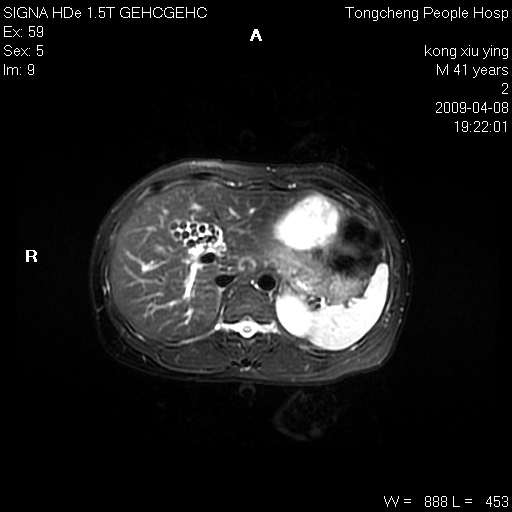

标题: CL1008:【经典】胆囊石榴籽样结石。

女,41岁。健康体检——彩超提示:胆囊显示不清。平素健康,无不适感。

腹部mr扫描及mrcp,图像如下: